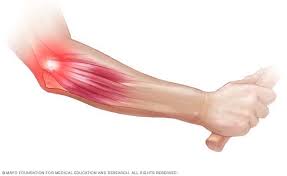

Teniszkönyök / golfkönyök (Lateral/medial epicondylitis)

A teniszkönyök, a könyök- és csukló-izület mozgatásakor jelentkező heves fájdalommal járó elváltozás a könyök külső területén. A fájdalom jellemzően az alkar külső felszínén elhelyezkedő a csukló és az ujjak nyújtásában közreműködő izmok irányába sugárzik, jellemzője a kéz szorítóerejének csökkenése, hirtelen jelentkező készsúrás szerű fájdalom. A kéz ügyetlenné válik, a beteg sokszor banális mozdulatokra is elejt tárgyakat.

A betegség oka a felkar könyök felőli végének az un. lateralis epicondylus területének csonthártya izgalma, illetve gyulladása. A gyulladást túlterhelés, fizikai munka váltja ki.

A golfkönyök a könyökizület belső felszínén, a csukló és kéz ujjak hajlító inainak tapadásánál kialakuló elváltozás, melynek oka és tünetei a teniszkönyökére hasonlítanak.

A kezelés első lépése a tehermentesítés, ami minden esetben jelentős időráfordítást, sok esetben munkából, szabadidős és sporttevékenységtől való távolmaradást is jelent.

A kezelés következő lépése az un. konzervatív kezelés, helyi hűtés, krémek alkalmazása, fizikoterápia, szájon át adott gyógyszerek. Újabban eredményesen alkalmazzuk ezen betegségek kezelésére a lökéshullám és lézer terápiát.

Harmadik lépésben helyileg adott injekciók javíthatnak a tüneteken, ez lehet steroid jellegű gyógyszer adása, de legújabban alkalmazható a saját vérből nyert un. thrombocytában dús plazma befecskendezése is, melynek során a szervezet saját védekező mechanizmusait használjuk fel a kezelés során.

A mennyiben a folyamat nem javul, vagy ismétlődik, műtéti megoldásre van szükség.